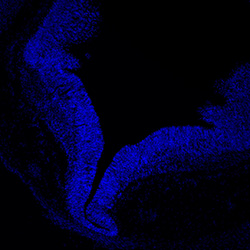

DAPI

6PCW human midbrain